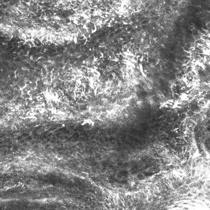

Confocal microscopy images

This is a collision tumour in which a melanoma in situ and a solar lentigo are both occurring in the same lesion.

These two diagnoses are different and separate, and this case demonstrates that if a partial sample biopsy is taken, you may miss the other diagnosis.